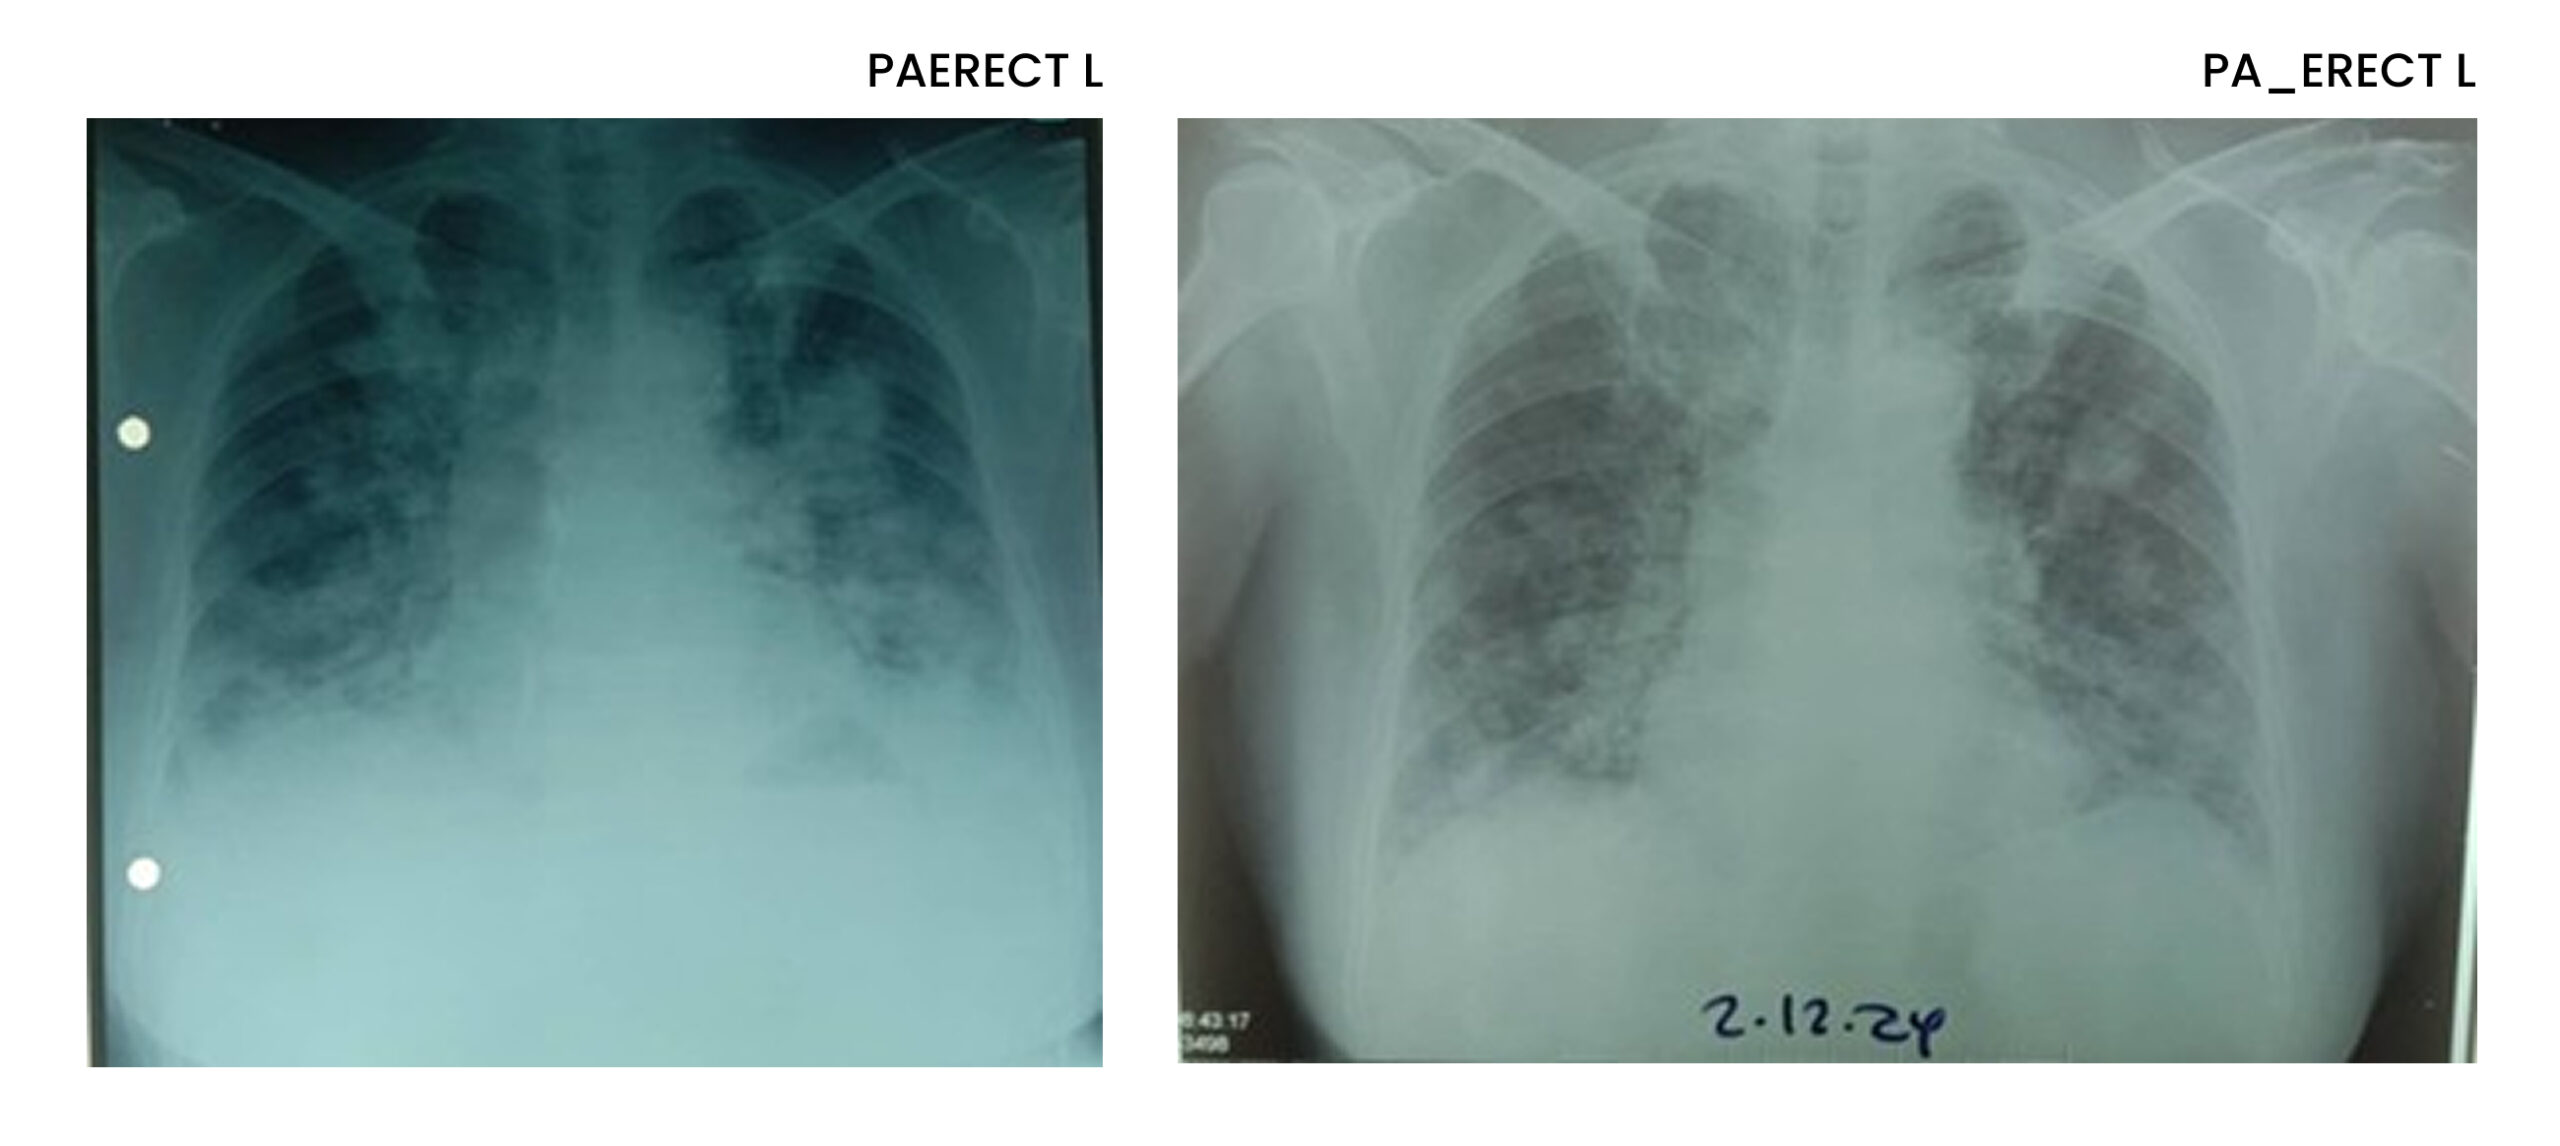

Physical examination and vital signs were unremarkable. Laboratory tests, including full blood count, liver function, and renal function, were at normal levels. Chest X-ray revealed multiple bilateral nodular opacities. (Figure 1) Sputum testing for Mycobacterium tuberculosis, including TB GeneXpert and culture, was negative. Despite completing a course of antibiotics, her symptoms and radiographic findings persisted.

Figure 1: CXR multiple bilateral nodular opacities